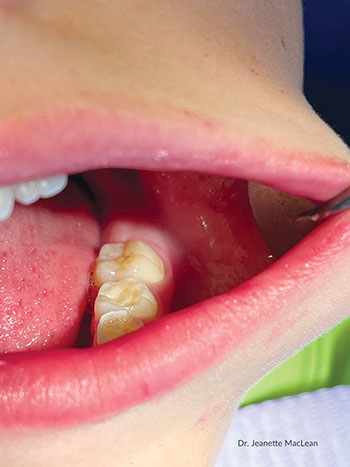

Patient 1: Buccal use

Curadont Cases

Fig. 1: A 9-year-old boy with buccal gumline decalcification on his first permanent molar.

Fig. 2: After cleaning the tooth, 37% phosphoric etch was applied for 20 seconds, then rinsed with water and dried.

Fig. 3: Curodont was applied and allowed to absorb for five minutes.

Fig. 4: A 16-month follow-up photo shows the buccal aspect of the tooth has not cavitated and the enamel translucency has improved.